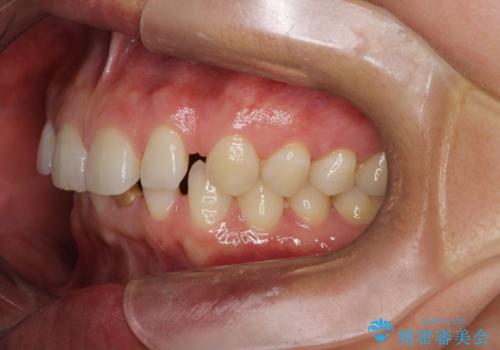

【空隙歯列】ワイヤー矯正で短期間に治療を終えたい

- 歯と歯の間に隙間があることを主訴に来院されました。

短期間での治療終了を希望され、ワイヤー矯正にて治療を行い1年ほどで治療を終了しております。

下顎前歯は矯正後補綴治療を行なっております。